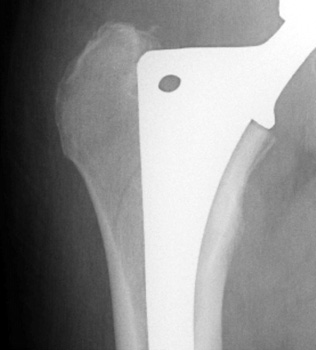

Intraoperative fracture of the proximal femur.

Intraoperative fracture of the femur at the tip of the femoral stem.

Femoral shaft fracture fixed with cerclage cables.